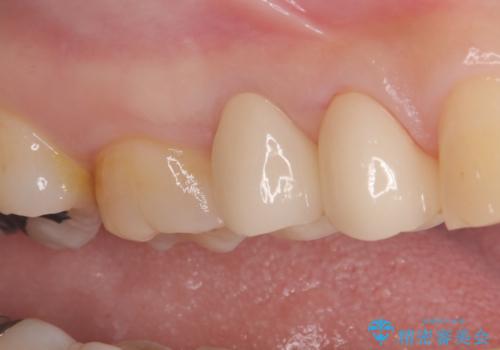

残存歯質を最大限に温存しつつ、フェルールを確保できるよう慎重に形成を行いました。

その後、型取りを行い、精密に適合するセラミッククラウンを作製しました。

クラウンの装着時には適合状態を確認し、接着操作を丁寧に行いました。

治療後は審美性と機能性の両面で良好な状態が得られ、患者様にもご満足いただけました。